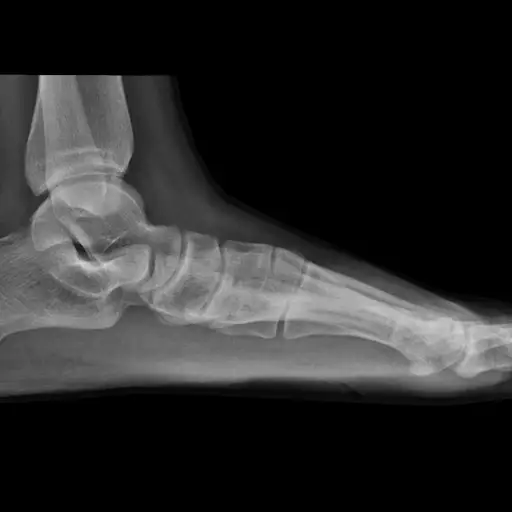

问题:拇僵直

这听起来像是伟哥过量的副作用,但拇僵直实际上是大脚趾关节的关节炎。症状包括大脚趾和脚之间的关节疼痛(当你迈步和推下时疼痛加剧);关节失去弹性;和炎症。你可以感谢时间老人,因为这些症状往往开始于30到60岁之间,因为多年的磨损和撕裂导致保护脚的软骨破坏,尽管遗传和先天性的畸形会加速这个过程。

拇僵直的解决方法

保守治疗包括冰敷、休息、矫形和非处方抗炎药。如果发现的足够早(在拇极限阶段),被称为唇切除术的手术可以改善活动,减少疼痛,挽救关节。但是,如果等待的时间太长,就会出现严重的关节炎。(多长时间太长因人而异,可以通过x光和症状来确定。)如果发生这种情况,你可能需要进行关节置换或关节融合,这几乎总是可以缓解疼痛,但也意味着你再也不能在那个关节处弯曲脚趾了。